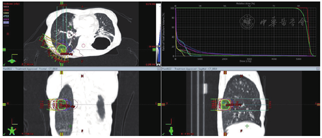

患者拒绝行CT引导下肺穿刺,未行化疗联合靶向治疗,于2016年6月行右肺转移灶精确放疗,仰卧位,负压袋固定体位,激光灯摆位,CT扫描,TPS优化放疗计划,IMRT技术,给予右肺转移灶精确放疗,5.0Gy/次,计划10次,总剂量50Gy。危及器官受量:脊髓最大受量4347cGy,心脏平均受量157cGy,右肺平均受量2622cGy,左肺平均受量474cGy,双肺平均受量289cGy,V20=5%(病例22图3)。放疗结束后胸部CT扫描示病变体积明显缩小,近期疗效PR优。放疗结束1个月,再次发现右肺新发转移,并再次给予大分割放疗(50Gy/10次,病例22图4),3个月后病情基本稳定,出现发热、咳嗽、胸闷、憋气,并逐渐加重,CT诊断为急性放射性肺炎(病例22图5),给予甲强龙,氧气吸入,抗感染,雾化等治疗好转后出院,失访。

3.经过选择的肺内单发转移或寡转移,SABR/SBRT不失为一种有效的治疗方法。治疗计划需评估好周围危及器官受照剂量和体积,具体可参考病例22图6。放射性肺炎是放疗后的严重不良反应,临床需特别注意预防和及时妥善处理。

4.再程或三程放疗需详细评估获益-风险。